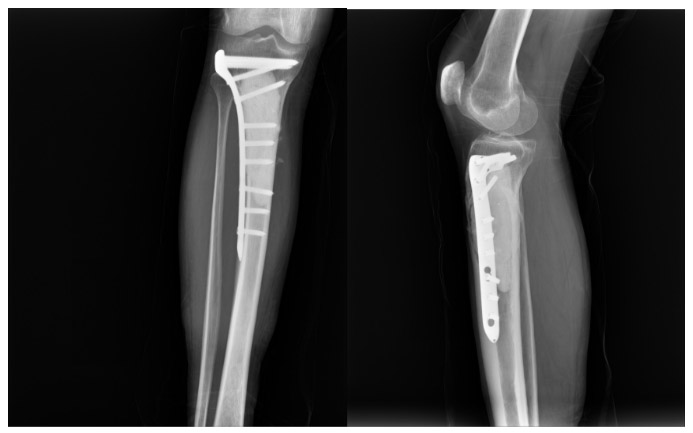

CASE 50: Laryngeal (Esophageal) cancer metastasis to the tibia

Post-surgery: The procedure involves removing the tumor, filling the resulting cavity with bone cement, and reinforcing it with an anatomical titanium plate.